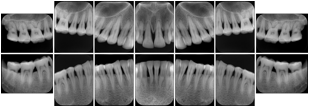

Intra-oral radiography typically involves acquisition of multiple images of various parts of the dentition. Many digital radiographic systems offer customized templates that are used for displaying the images in a study on the screen. These templates may also be referred to as mounts or view sets. The Structured Display Object represents a standard method of encoding and exchanging the layout and intended display of Structured Displays. A structured display object created in this manner could be stored with a study and exchanged with images to allow for complete reproduction of the original exam.

1. A patient visits a General Dentist where a Full Mouth Series Exam with 18 images is acquired. The dentist observes severe bone loss and refers the patient to a Periodontist. The 18 images from the Full Mouth Series along with a Structured Display are copied to a DICOM Interchange CD and sent with the patient to see the specialist. The Periodontist uses the CD to open the exam in his Dental Radiographic Software and consults via phone with the General Dentist. Both are able to observe the same exam showing the images on each user's display using the exact same layout.

Intra-oral Full Mouth Series Structured Display

Figure OO-1. Intra-oral Full Mouth Series Structured Display